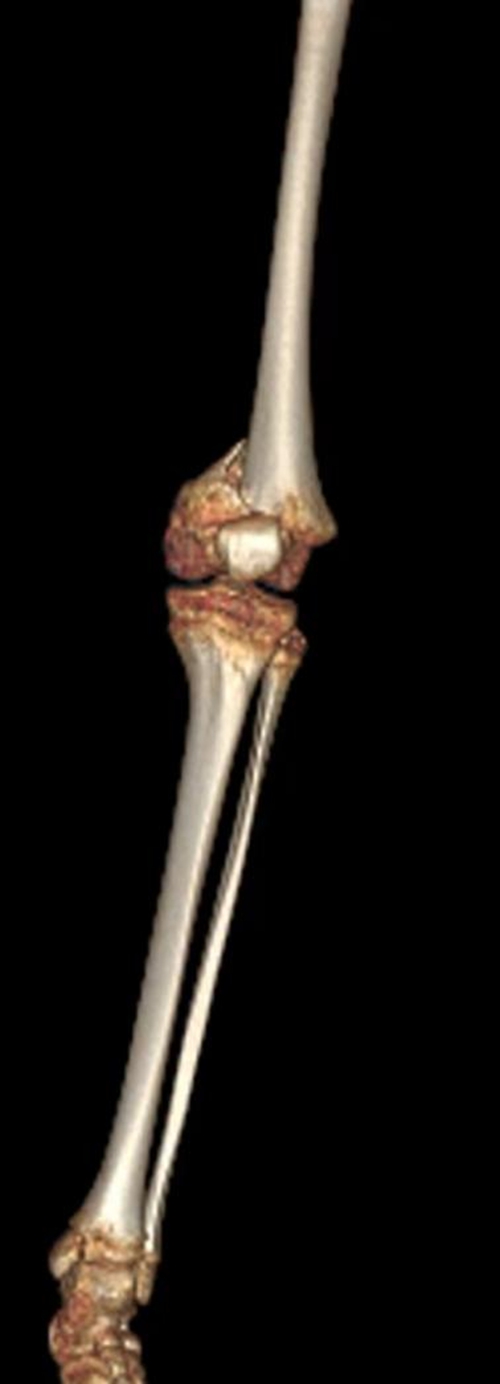

△術(shù)前CT

骨科接診患兒后

即刻評估病情

高處墜落導(dǎo)致明明

全身多處骨折

頜骨斷成了4塊

張口嚴(yán)重受限

左股骨完全斷裂

左脛骨、腓骨也發(fā)生骨折